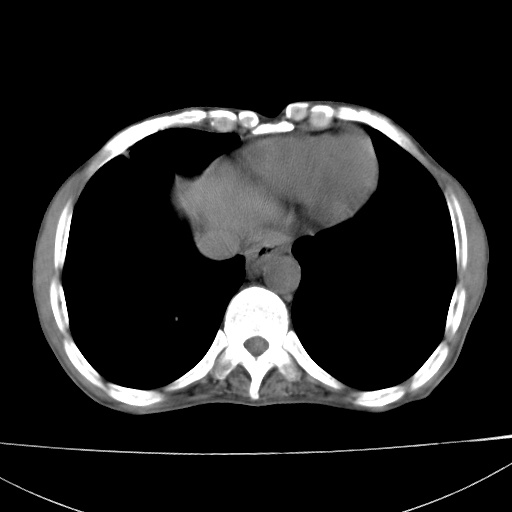

患者 男  41岁,右上腹痛伴腹泻10天,8年前有乙肝,本次b超查肝右叶占位来做ct ,请会诊!

肝硬化\\脾大\\门静脉高压,胃底静脉曲张可能性大.肝右叶肝癌肝内转移,建议增强.左侧小结石.

1)考虑肝癌;建议行ct增强扫描检查。2)脾大,门静脉高压,胃底静脉曲张。3)左肾小结石。

1)考虑肝癌及门脉瘤栓,建议行ct增强扫描检查。2)脾大,门静脉高压,胃底静脉曲张。3)左肾小结石。

1)考虑肝癌;2)脾大,门静脉高压,胃底静脉曲张。3)左肾小结石。建议行ct增强扫描检查。